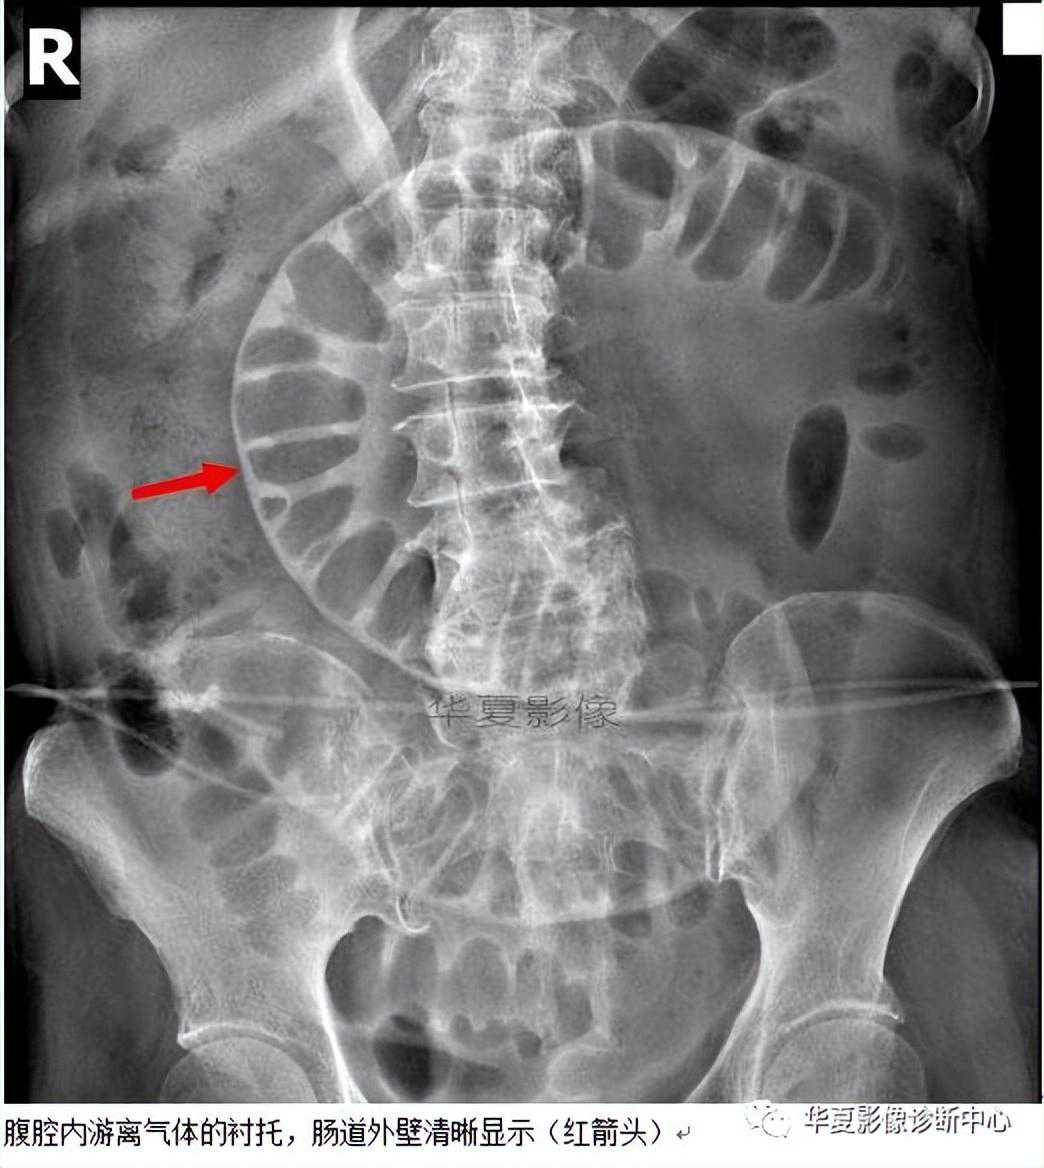

【影像表现】在仰卧位腹部X线平片上,胃肠道腔内气体显示内壁的同时,气腹可将胃肠道外壁显示出来。

【征象解释】正常情况下气体仅显示肠壁内腔表面的轮廓而不显示浆膜表面,胃肠道外壁的密度类似邻近腹腔的内容物。然而,当腹腔内有适量的自由气体存在时,这些自由气体更可能集中在肠撵间,因此可以见到肠管的外壁,这就是双壁征的典型表现。当肠腔充满液体,内璧不可见,只有外侧壁是可见时,表现为不典型的双壁征。

研究表明,发现少量腹膜腔游离气体敏感的方法是立位胸部照片,能迅速评价幅下游离气体。在大多数医疗机构中,立位胸部照片是常规证实部分急腹症的方法。对不能站立的患者,一种替代方法是左侧卧位。结果表明优质的侧卧位片与站立位胸部照片一样,能发现1ml的腹膜腔内自由气体。CT能发现1ml的游离气体,并能帮助证实平片可疑的气腹。但是,婴幼儿或者ICU的患者经常只能行仰卧位腹部照片。这种情况下认识双壁征至关重要。气腹有许多可能的平片表现,最普通的征象是右隔下游离气体,因为肝脏高密度轮廓的勾画使其比较明显。双壁征是气腹在卧位照片第二个最普通的征象,有3%的发生率。不常见的游离气体征象包括三角征、肝缘征、X镰状韧带征、足球征、倒V征和脐尿管征等。

与双壁征类似表现并不少见,有必要区别真阳性双壁征与一个没有气腹征的假阳性双壁征。双壁征有时能被邻近的肠襻干扰,因而在肠襻的内部也可出现相邻肠襻壁的轮廓,导致误诊为游离气体;最近经过腹部CT研究的患者中,少数剩余的增强剂覆盖在肠腔内表面也可增加肠壁密度形成假双壁征;假阳性双壁征也可以由Mach带导致;在不明确的病例,也可以通过左侧卧位照片或立位腹部照片来证实。

总之,气腹常提示潜在的严重腹腔内疾病,危重患者经常只是行卧位照片,在卧位照片上通过认识双壁征发现游离气体能提供重要的治疗信息。